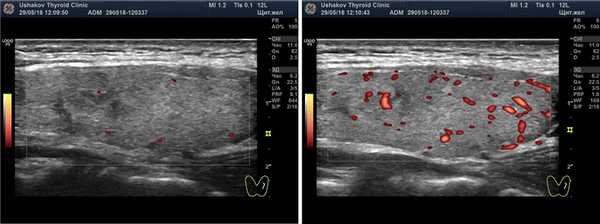

Рисунок. 7. Неупорядоченный кровоток узлов щитовидной железы.

Клиника щитовидной железы доктора А.В. Ушакова ввела такой признак оценки кровотока как его «упорядоченность». Под упорядоченностью кровотока узла понимается расположение сосудов в соответствии с естественным сегментарным устройством ткани узла. Упорядоченность кровотока узлов может быть в разной степени выражена. Беспорядочный кровоток (т.е. независимо от сегментов) относится к важному признаку злокачественности ткани узла. Такое беспорядочное расположение сосудов возникает при неравномерном и несегментированном прорастании сосудов вместе с образованием раковой ткани.